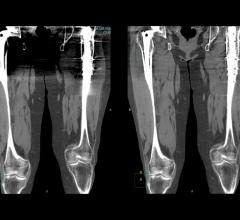

Radiation exposure from multidetector computed tomography (CT) has become a pressing public health concern in both lay and medical publications. Implementation of iterative reconstruction offers the ability to minimize radiation exposure while preserving and, in some cases, improving image quality. However, in order to evaluate iterative reconstruction software, one must first understand the basics of how it works.